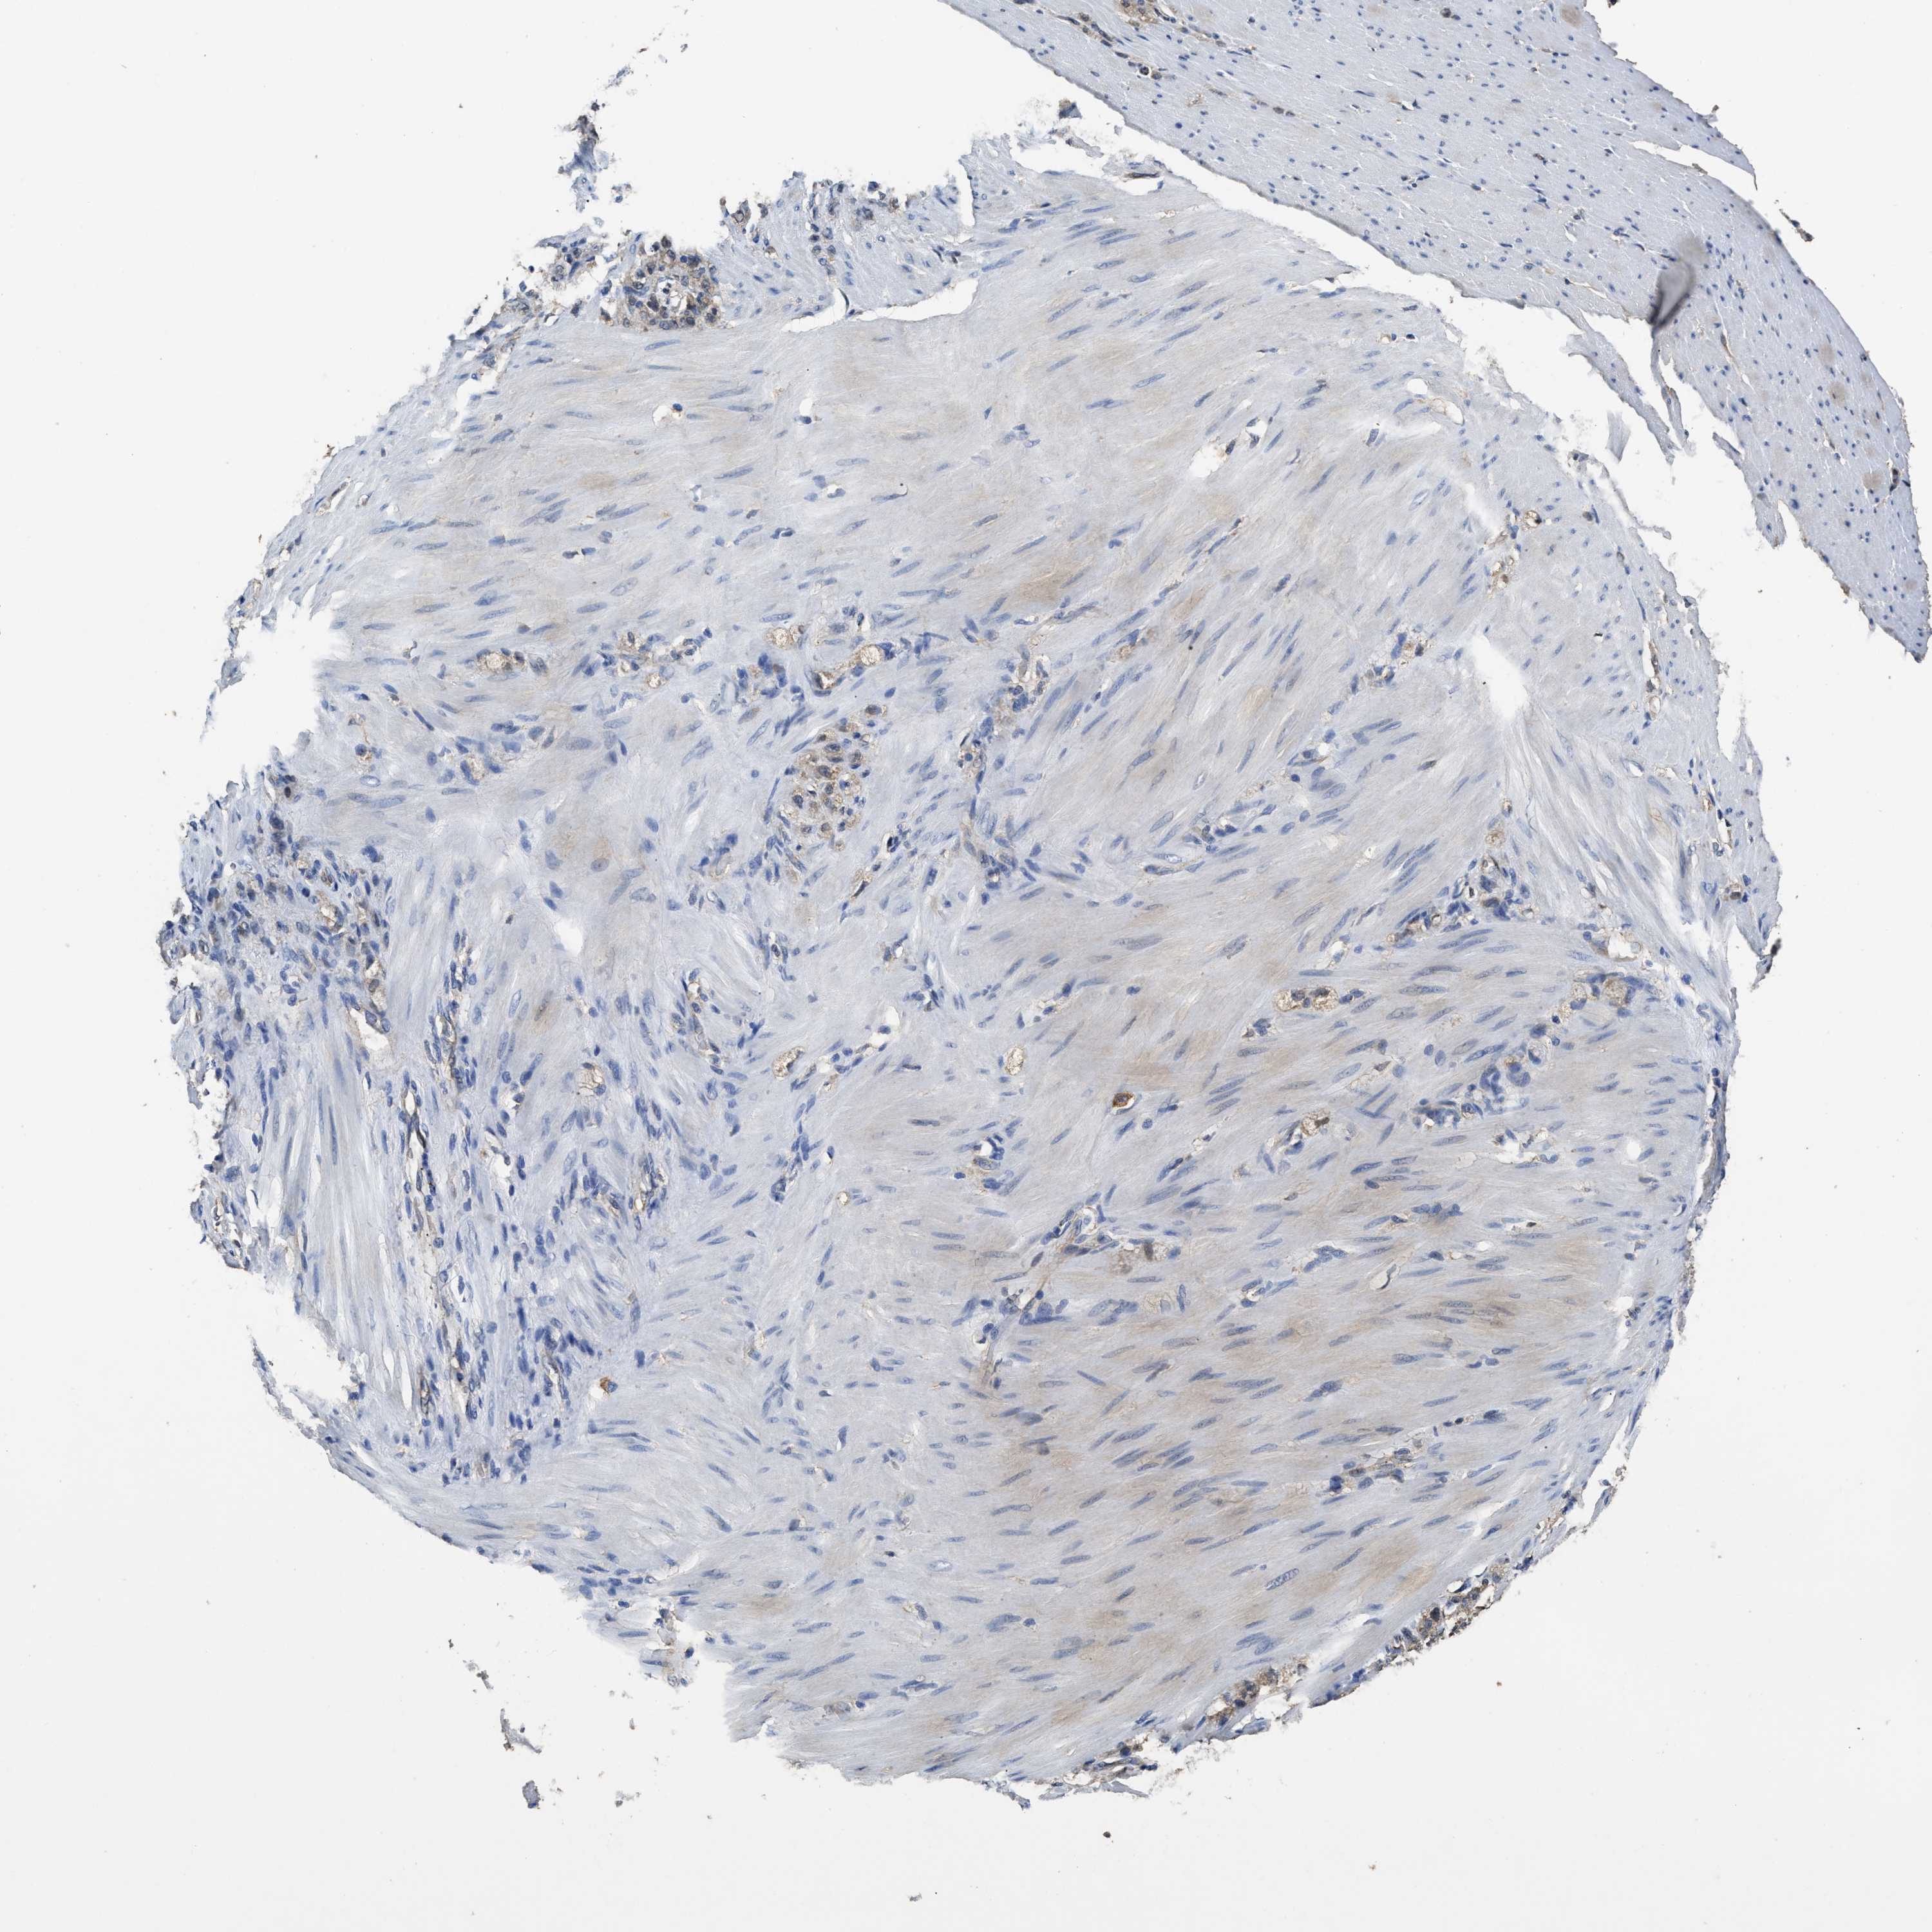

STOMACH CANCER - Protein expressioni

A mouse-over function shows sample information and annotation data. Click on an image to view it in a full screen mode. Samples can be filtered based on level of antibody staining by selecting one or several of the following categories: high, medium, low and not detected. The assay and annotation is described here.

Note that samples used for immunohistochemistry by the Human Protein Atlas do not correspond to samples in the TCGA dataset.

Antibody stainingi

Antibody staining in the annotated cell types in the current human tissue is reported as not detected, low, medium, or high, based on conventional immunohistochemistry profiling in selected tissues. This score is based on the combination of the staining intensity and fraction of stained cells.

Each image is clickable and will lead to virtual microscopy that enables deeper exploration of all samples and also displays staining intensity scores, fraction scores and subcellular localization as well as patient and tissue information for each sample.

Antibody HPA008445

Antibody CAB016200

Antibody CAB021109

Antibody CAB047350

Staining

High

Medium

Low

Not detected

Intensity

Strong

Moderate

Weak

Negative

Quantity

>75%

75%-25%

<25%

None

Location

Nuclear

Cytoplasmic/membranous

Cytoplasmic/membranous,nuclear

Adenocarcinoma, NOS

Adenocarcinoma, High grade